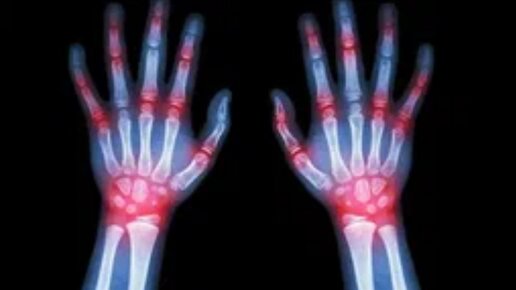

Ревматизм рук. Что такое ревматическая лихорадка?

Ревматизм рук – болезнь, которая характеризуется аутоиммунным воспалением в соединительной ткани. Заболевание имеет локализацию не только в суставах рук, но и в сердечно-сосудистой системе. Это происходит по причине попадания в организм стрептококков и дальнейшей патологической реакции иммунной системы. Клетки иммунитета, атакуя чужеродную инфекцию, могут нападать на здоровые клетки, что приводит к воспалению и развитию ревматизма. Сегодня мы расскажем подробно об этом заболевании. Причины возникновения...